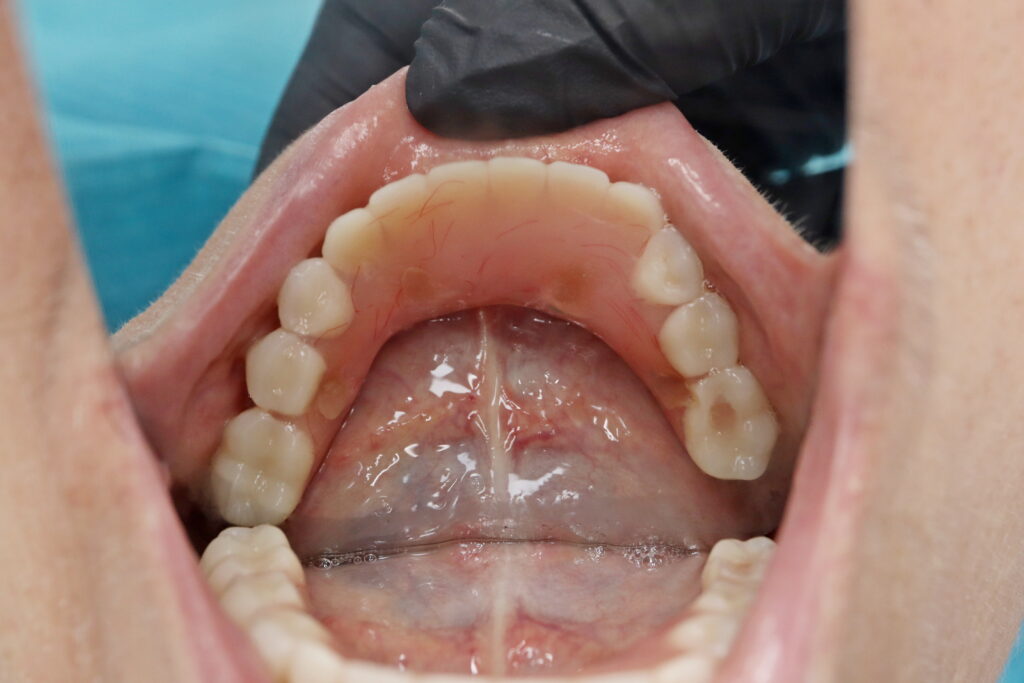

Ситуация до лечения

Жалобы: Пациент обратился к нам с целью изготовления съемных протезов после консультации в сторонней клинике.

Диагноз: Полная адентия верхней челюсти и частичная вторичная адентия нижней челюсти.

пациент до имплантации